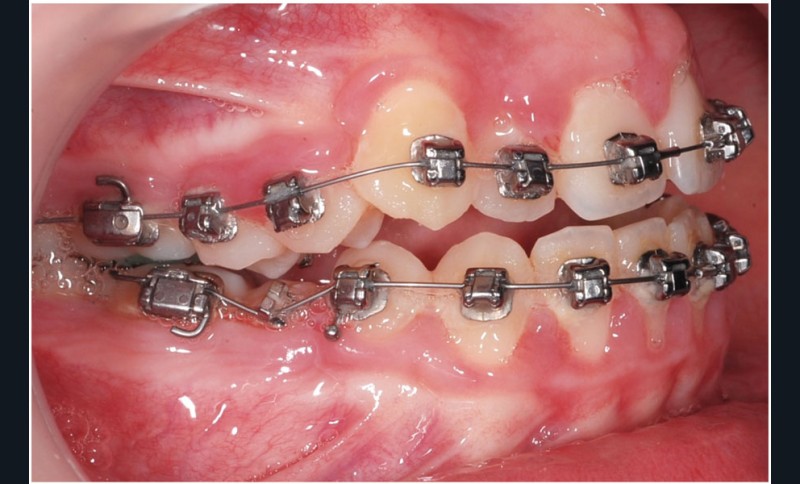

Le cas d’Anthony âgé de 11 ans et 7 mois qui présente une endomaxillie bilatérale associée à un léger encombrement mandibulaire dans un contexte de classe I squelettique hyperdivergente (fig. 1 à 10) est très représentatif de ce que peuvent apporter les forces légères appliquées aux alvéoles dentaires tout en intégrant des torques spécifiques qui permettent de contrôler parfaitement l’orientation radiculaire (fig. 11 à 29).

Le système laisse beaucoup de liberté dans l’interface entre bracket et arc : la vascularisation, et donc le recrutement cellulaire et la reconstruction osseuse s’en trouvent améliorés, la mise en place de l’occlusion se fait sous le contrôle de la matrice fonctionnelle, car les forces engagées restent en dessous de la puissance des forces masticatrices notamment.